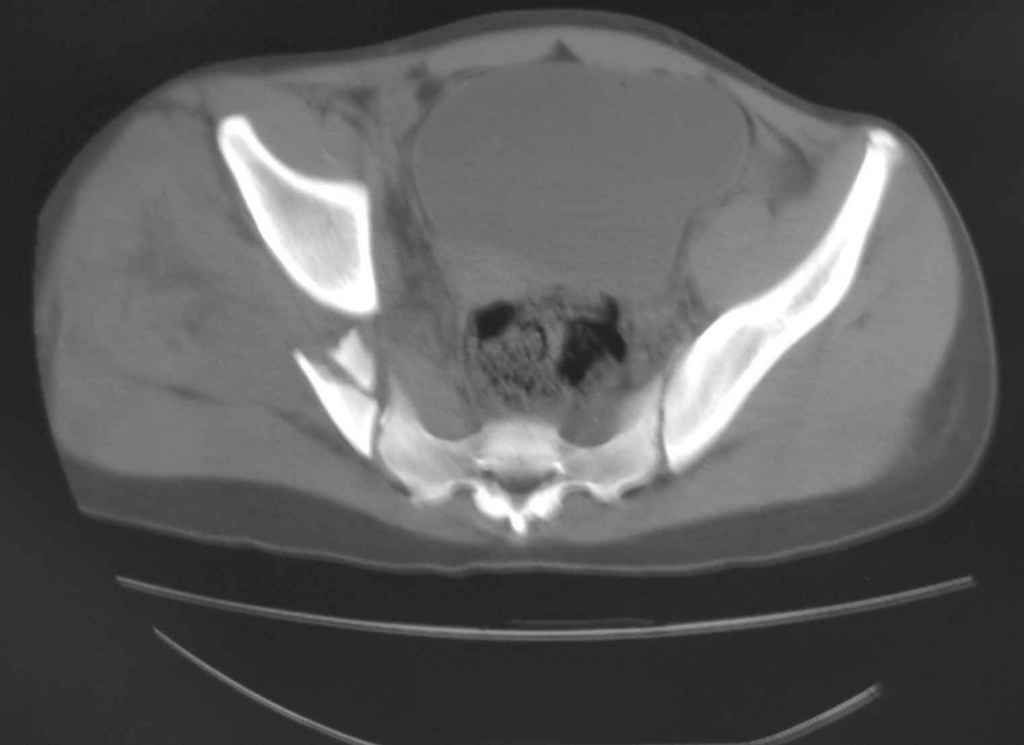

Принципиально важно видеть все срезы КТ через вертлугу, так как тактика лечения будет в первую очередь обусловлена характером перелома ветрлужной впадины, во вторую - вертикальным смещением таза ( где варианты - от банального скелетного вытяжения до ВЧКО или накостного остеосинтеза - в основном зависит от пресловутой "позиции кафедры")

Уважаемый Алексей, на представленных Вами снимках имеется вертикально-нестабильное повреждение тазового кольца без повреждения вертлужной впадины. Учитывая это, а так же растущий возраст ребенка я бы выбрал аппарат внешней фиксации в виде кольцевой опоры, т.к. не смотря на оскольчатый перелом крыла в переднем отделе можно ввести минимум 2 стержня + 1-2 надвертлужно. Этого будет достаточно чтобы "зацепится", выполнить репозицию и дальнейшую фиксацию. Перелом шейки по моему лучше прооперировать 3 канюлированными винтами по АО.

Таз - подвздошным и падлобковым доступом раздельные рекострукционные пластины 4 штуки. Сплошную пластину как у взрослых нельзя (из-за роста придется доставать)